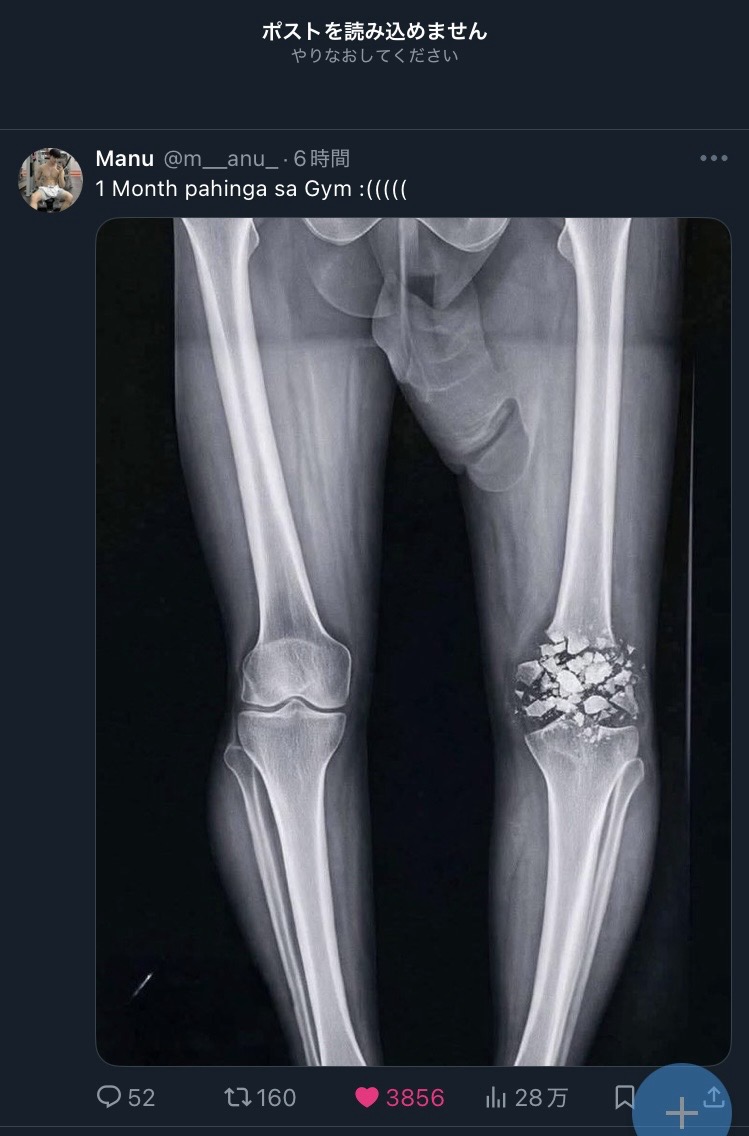

よく見たら全然笑えないレントゲンだった

>よく見たら全然笑えないレントゲンだった

よく見なくてもさすがに膝の方が先に目につくだろ!?

1ヶ月でどうにかなるようには見えない

不健全な「」の9割はX-RAYチンポに視線を取られて粉砕骨折に気が付かない

こんな綺麗に粉々の状態で映るもんなのか…?

ヒビとかバキンと割れるとかじゃなくこんな粉々になるって何したんだ…

破片全部取り除いて骨の代わり入れないとダメだな…

ここまで粉みじんになることってあるのか…

骨がこんな風に綺麗に砕けるわけないだろう

レントゲンじゃなくてCGイラストだよ

粉砕骨折を文字通りのイメージするとこういう感じになりそう

バーベル落としたとかかな?

>1ヶ月でどうにかなるようには見えない

1か月どころかもう一生治らねえ程度じゃねえかこれ?

皿が粉々だ

砕けてもこんな綺麗には写らないんだろうな

そもそもAIだからこの状態のやつはいない

骨は内部に結合組織を持ち意外に柔軟なのでこんな硬いもののような割れ方はしないし折れ方も形状や靱帯の付き方受傷機転からくる特徴が必ずある

なのでそれらすべて無視してる画像はどうみてもフェイクというかジョーク